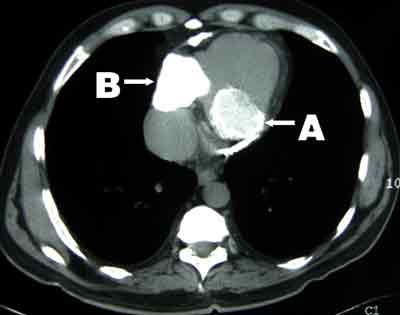

A 58-year-old man of British descent presented in 2003 with chest pain, facial flushing and elevated jugular venous pressure but no leg oedema. He had been exposed to tuberculosis in childhood, had a strongly positive tuberculin test and had been followed up in the tuberculosis surveillance program with regular chest x-rays, but had never been diagnosed with tuberculosis. Chest x-ray on presentation showed calcified plaques and masses in the pericardium and mediastinum (Box 1). Computed tomography revealed extensive calcification of the pericardium (Box 2). Coronary angiography showed 70% stenosis in the left anterior descending artery. Cardiac catheterisation showed equalisation of diastolic pressures in all four chambers, with a positive square root sign (pattern of ventricular diastolic pressure characteristic of constrictive pericarditis).

Pericardiectomy with left internal mammary bypass graft to the left anterior descending artery was performed. Severe constrictive pericarditis with a thick (up to 4 mm) layer of calcium plaque was found. Two large cystic masses within a thick calcified shell were present in the posterolateral aspect of the right side of the heart and the left posterior atrioventricular groove. Both contained creamy caseous material, which was drained (Box 3). Histopathological examination was consistent with chronic calcific pericarditis with no granuloma. Microbiological examination and culture did not show any organisms.